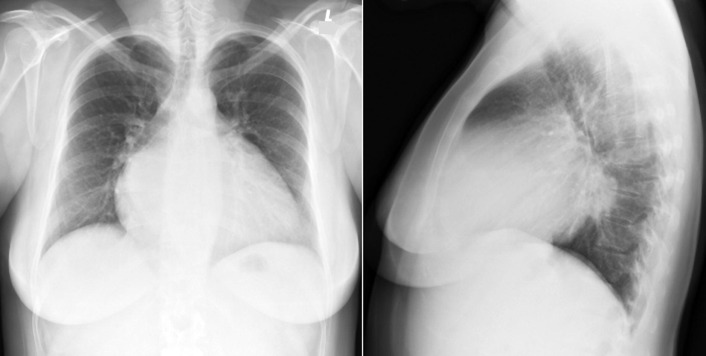

The radiographic findings of mitral stenosis ( Graphic 15-1 ; Figs. 15-1 to 15-16 ) reflect the pressure overload of the left atrium and pulmonary veins, and later of the right heart. As well, the commonly associated chronic atrial fibrillation contributes to (bi)atrial dilation. Associated rheumatic valvular lesions such as mitral regurgitation, tricuspid regurgitation, aortic insufficiency, and aortic stenosis/aortic insufficiency are common, and they alter the appearance of the heart.